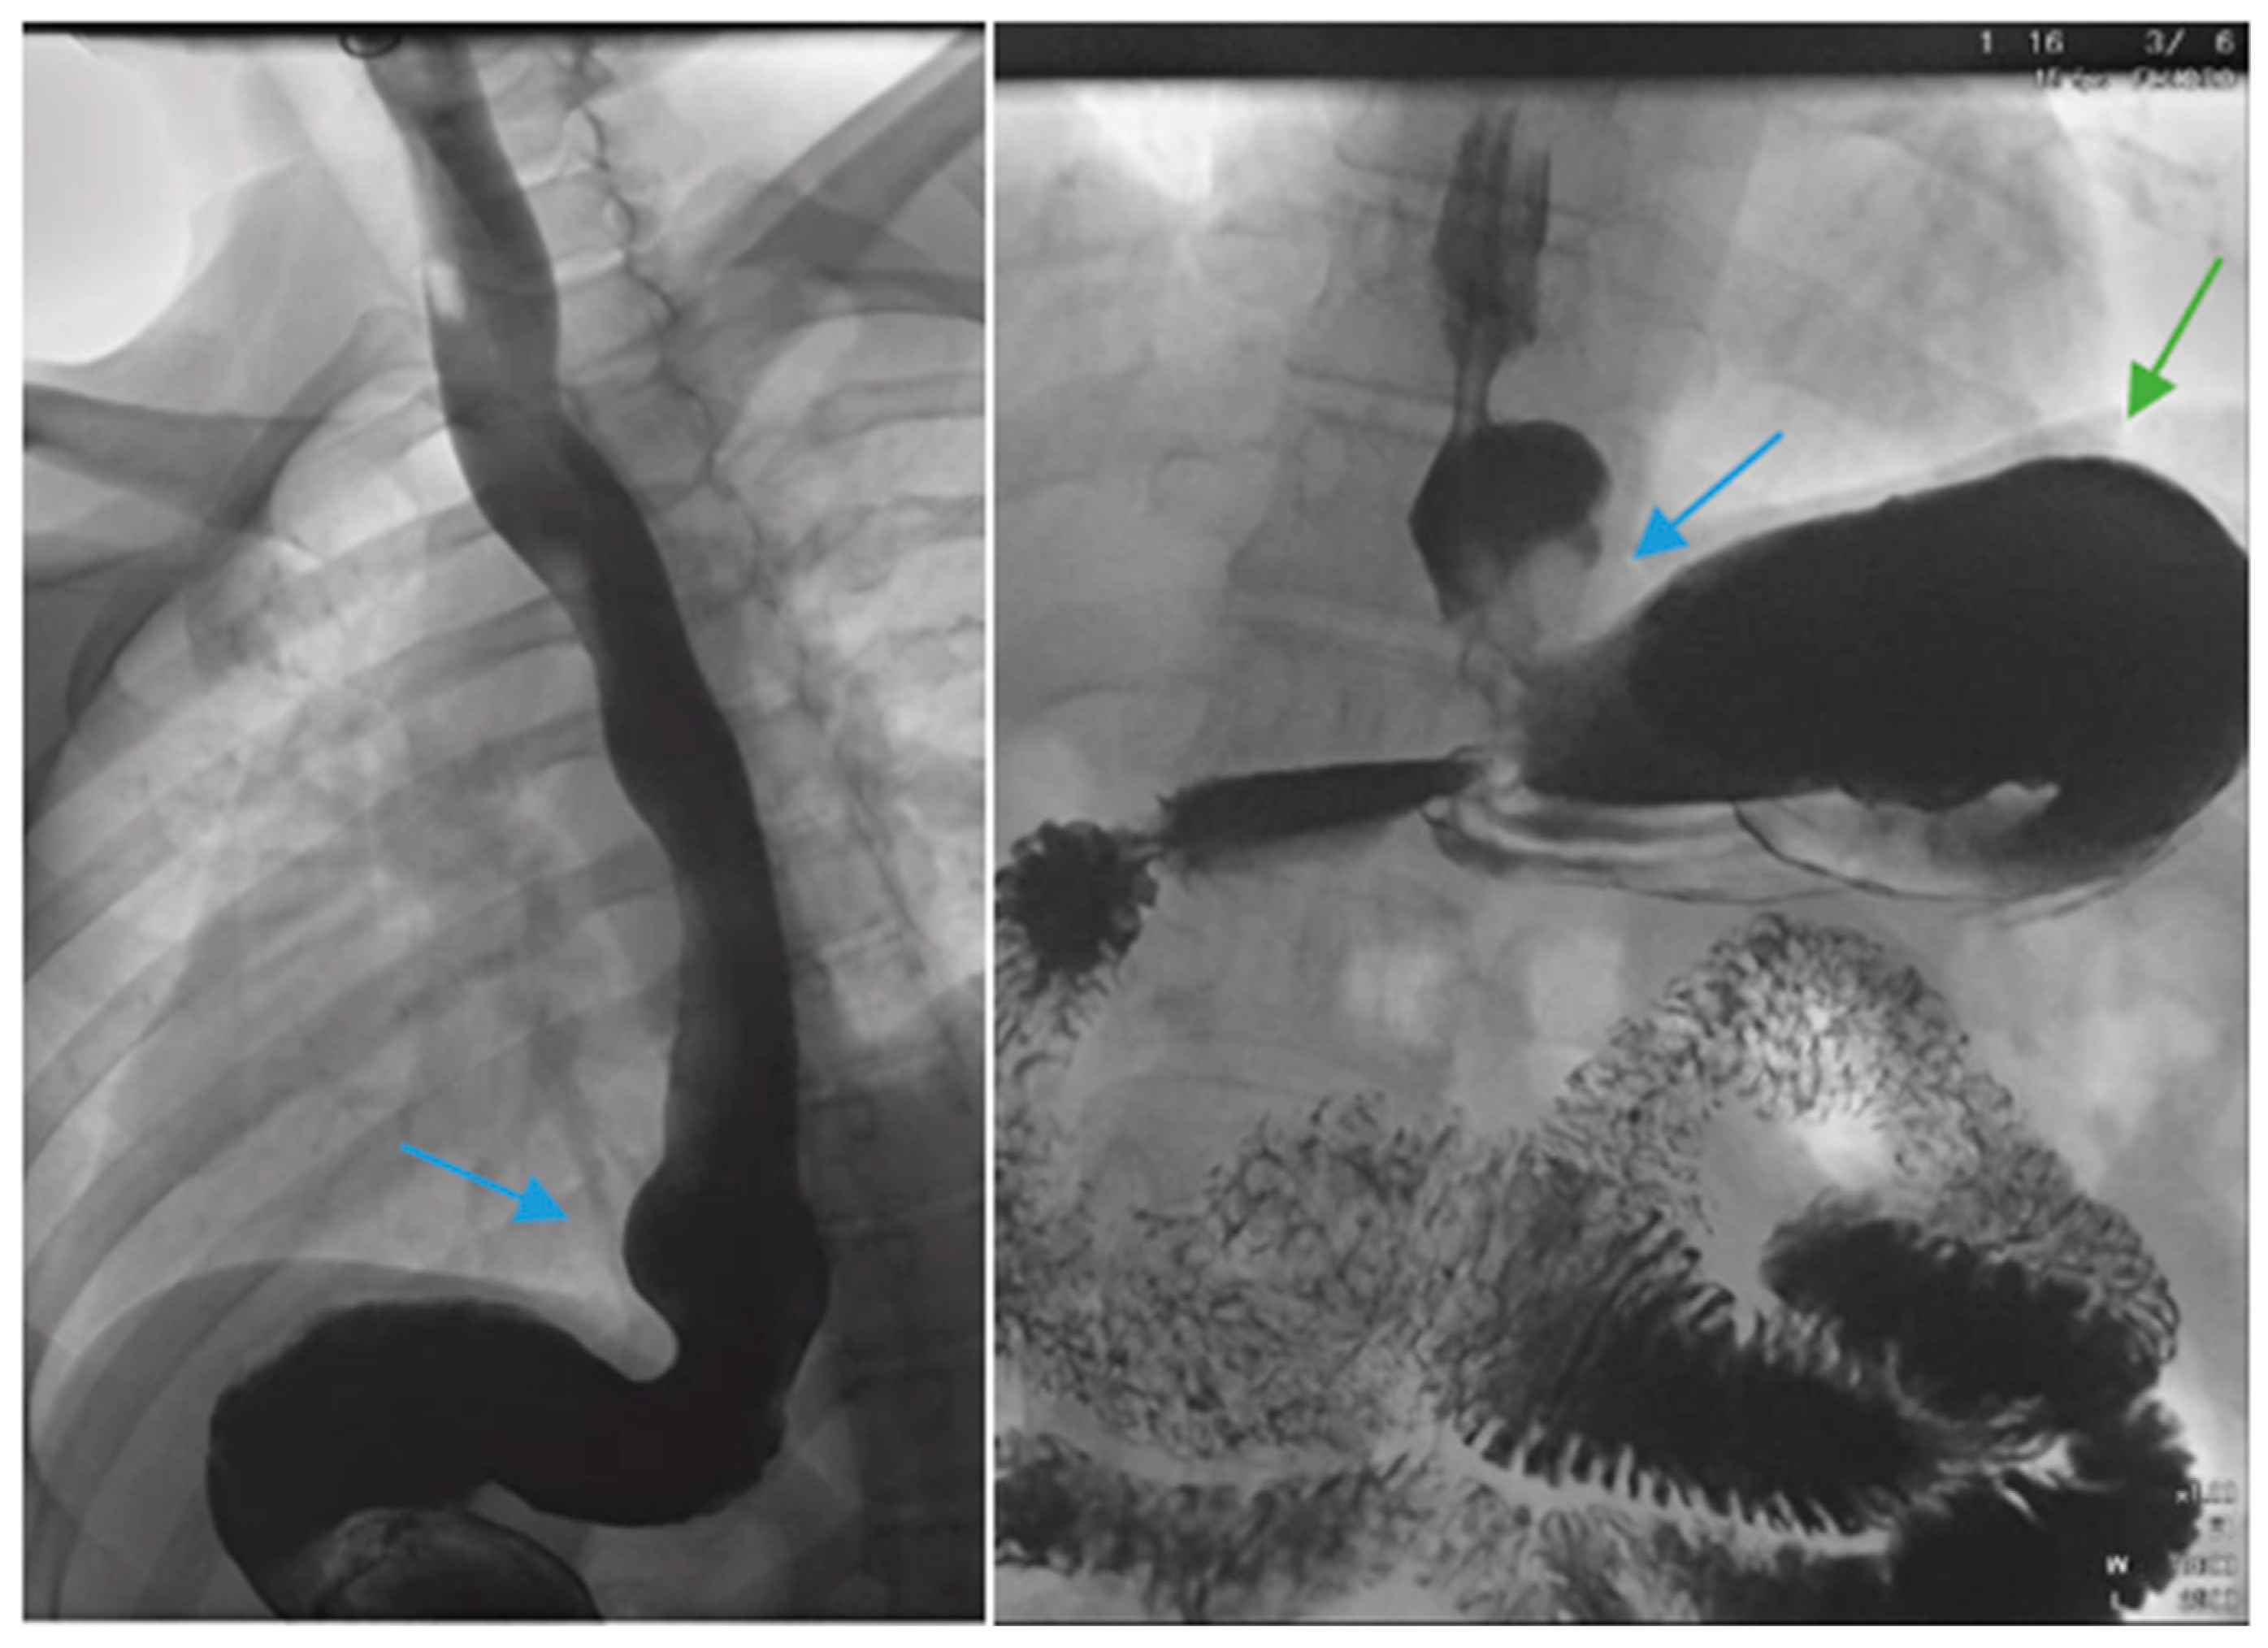

Figure 1.

Upper gastrointestinal series in a patient post-sleeve gastrectomy with early satiety and reflux reveals the following: a small, hiatal hernia and gastroesophageal reflux (blue arrow, left) in addition to abnormal angulation (blue arrow, right) and dilation of the gastric sleeve (green arrow, right). The patient underwent conversion to Roux-en-Y gastric bypass with marked clinical improvement.

Figure 2.

An upper gastrointestinal series reveals a moderate, sliding type-one hiatal hernia (bottom arrow) in addition to gastroesophageal reflux disease (top arrow) in a patient with morbid obesity.

Complications of SG, including stenosis, angulation or kinking, are associated with increased intragastric pressure and GERD (Figure 1) [38]. Data regarding the optimal bougie size for weight loss and reduced reflux are mixed, but generally support a range of 36–42 French [39,40,41,42,43]. Overfilling of the gastric sleeve due to a large meal portion may result in reflux symptoms, and thus, patients should be counseled to gradually advance their diet from liquids to small portions of healthy, protein-rich foods. The gastric sleeve dimensions should be sufficient, as too narrow of a gastric sleeve may result in increased intragastric pressure and subsequent reflux. An abnormally narrow sleeve may also lead to regurgitation due to overfilling, even in patients with a competent lower esophageal sphincter and no hiatal hernia. Felinska et al. described the ideal shape of a gastric sleeve to be a trapezoid with a wide antrum and a narrow cardia to prevent sleeve stenosis or increased pressure within the stomach [34]. Furthermore, the preservation of the antrum has been suggested to increase gastric emptying and reduce subsequent GERD [44]. Esophagogastric dysmotility may be a contributing factor to post-SG GERD and a dynamic contrast study can be a useful test in establishing the diagnosis.